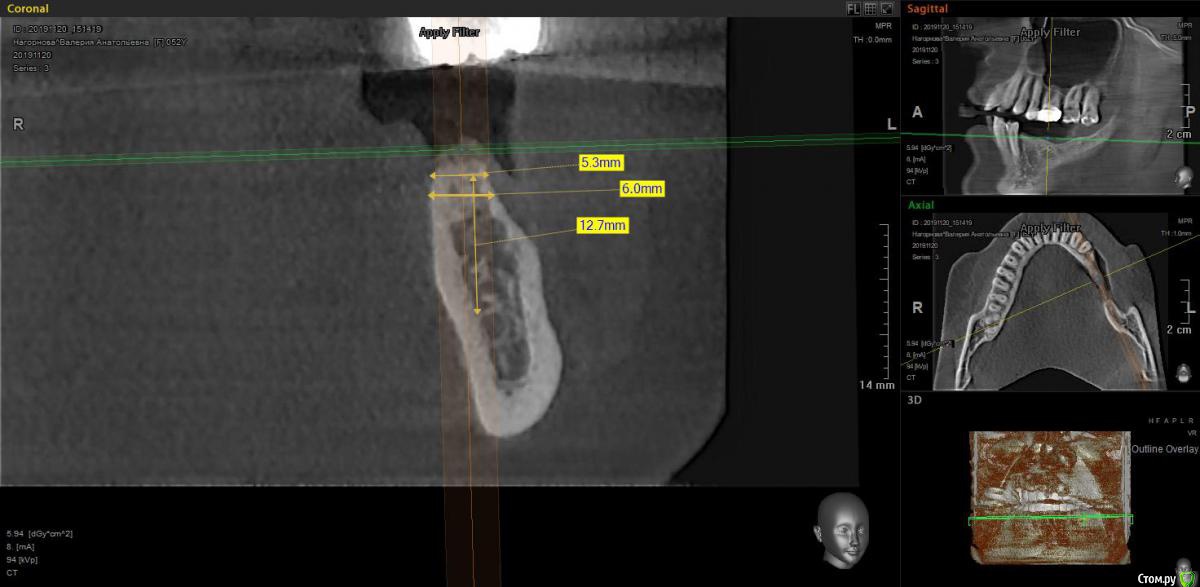

moises Опубликовано 5 декабря, 2019 Автор Поделиться Опубликовано 5 декабря, 2019 так какая там ситуация в области 36? что там с костью и слизистой? и вы уверенны с позицией 37? он смотрит в щечный бугор 27! сделайте фото, покажите больше срезов, с ортопедом продумайте все варианты протезированияи уверен, вам подскажут хороший вариант протезирования. вы вопрос поставили конкретный "мембрану или смартбилдер" и Александр верно вам ответил хотя осмелюсь предположить, сам бы он выбрал другой вариант ))) на ankylosСместить язычнее-выраженное поднутрение .Или ось сместить,чтобы выйти на небный бугор 26?Протезировать буду сам. Ситуация в области 36 Ссылка на комментарий

Дмитрий М Опубликовано 5 декабря, 2019 Поделиться Опубликовано 5 декабря, 2019 Сместить язычнее-выраженное поднутрение .Или ось сместить,чтобы выйти на небный бугор 26?Протезировать буду сам. Ситуация в области 3636.jpgпо хорошему ось имплатнта должна соответствовать оси нагрузки и учитывать вариант фиксации (что вы планируете, винтовая или цемент) как по мне, так вариант 35,36+консоль интереснее! кости вагон, смотрите уровень заглубления импланта по будущим зенитам, создайте зону прикрепленой десны.НО опять же, смотря что будет вверху. Судя по снимку зубоальвеолярное выдвижение 25, 26, 27; 28 на выход! сколько места для коронок 35, 36? Сколько прикрепленной десны? планируйте имплантацию в зависимости от конечного варианта протезирования. Ссылка на комментарий